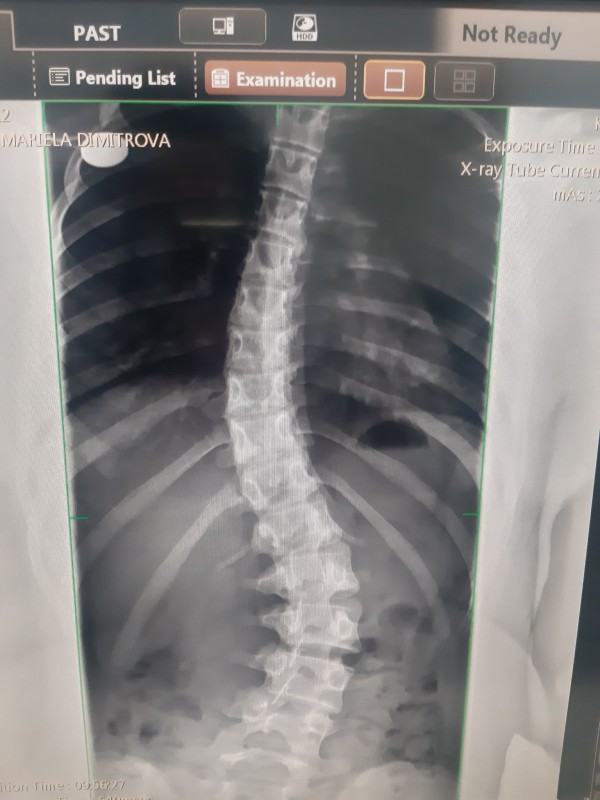

13-годишната Мариела Димитрова от град Казанлък има нужда от спешна операция. Детето е диагностицирано със сколиоза, съобщава нейната майка Таня Димитрова.

Сколиозата е заболяване на гръбначния стълб, при което гръбнака се изкривява настрани. При изкривявания по-големи от 45-50° или ако заболяването прогресира много бързо, какъвто е и случаят със Мариела, оперативната намеса е наложаща. В противен случай пространството в гръдния кош, поради деформирането на прешлените започва да се изменя и осуква, което води до ограничаване на правилното функциониране на белите дробове и сърцето, изтръпване на крайниците, болки и в не редки случаи пълна инвализация.